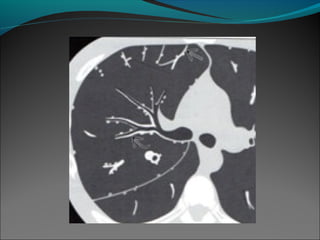

Bronquiectasias quísticas y varicosas en un paciente con asma severo crónico

Bronquiectasias quísticas yvaricosas en un paciente con asma severo crónico